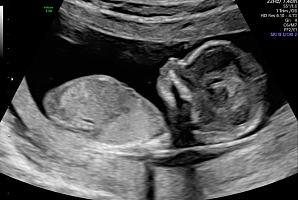

С помощью ультразвукового исследования во время беременности врач может оценить нормальную анатомию плода, размеры органов и структуру, их взаиморасположение, определить маркеры хромосомных патологий или аномалии органов плода, а также строение плаценты, объем околоплодных вод и строение пуповины. Ультразвуковой метод – это основной и первый метод, дающий информацию врачу акушеру-гинекологу и влияющий на результат биохимического скрининга.

УЗИ проводится на сроке 11–14 недель, чтобы:

• оценить анатомию органов плода;

• увидеть грубые пороки развития и / или признаки генетических аномалий (которые потенциально могут потребовать прерывания беременности).

УЗИ проводится на сроке 18–21 неделя, чтобы:

• более точно оценить строение внутренних органов плода;

• выявить аномалии развития и / или своевременно диагностировать возможные инвалидизирующие заболевания.

УЗИ на этом сроке беременности позволяет диагностировать или исключить до 80-90% патологий у плода.